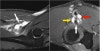

The common extensor tendon originates at the lateral epicondyle. On a T1W-images the tendon should have a low signal intensity (yellow arrow).

On a T1W-images the tendon should have a low signal intensity (red arrow).